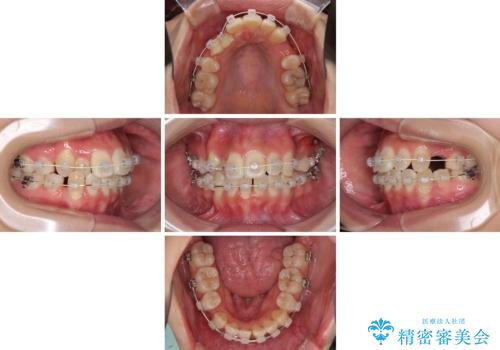

- 八重歯を気にして来院された患者様です。

上下ともに前突感と叢生が認められ、上顎の正中が著しく右側にずれていたため、上下左右第一小臼歯4本を抜歯し、ワイヤー矯正にて治療を行うこととしました。

移動量が多かったため、治療期間は通常より半年~1年ほど長くかかりましたが、上下の正中をほぼ同じ位置にまで移動させることができました。